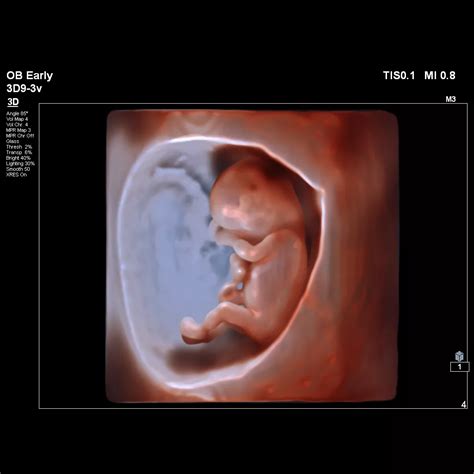

The advancement of medical technology has brought about remarkable innovations in prenatal care, allowing expectant parents to gain deeper insights into their baby's development. One of the most fascinating developments in this field is the ability to visualize a 14W fetus face 3D image. This technology not only provides a clearer picture of the baby's features but also offers a range of benefits for both medical professionals and parents.

The 14th week of pregnancy is a crucial stage in fetal development. By this point, the fetus has undergone significant changes, and many of its features are becoming more defined. The baby's face, in particular, starts to take shape, with the eyes moving closer together and the ears becoming more prominent. The 14W fetus face 3D imaging technology captures these details with remarkable clarity, providing a detailed view of the baby's facial features.

3D ultrasound technology uses sound waves to create detailed images of the fetus. Unlike traditional 2D ultrasound, which produces flat images, 3D ultrasound captures multiple images from different angles and combines them to create a three-dimensional view. This process involves several steps:

• Sound Wave Emission: The ultrasound machine emits high-frequency sound waves that penetrate the mother's abdomen and bounce off the fetus.

• Data Collection: The reflected sound waves are captured by the ultrasound transducer and converted into electrical signals.

• Image Processing: The electrical signals are processed by a computer to generate a 3D image of the fetus.

• Visualization: The 3D image is displayed on a screen, allowing healthcare providers and parents to view the fetus in detail.

For a 14W fetus face 3D image, the process is similar, but the focus is on capturing the facial features of the fetus. This requires a skilled technician to position the transducer correctly and adjust the settings to optimize the image quality.